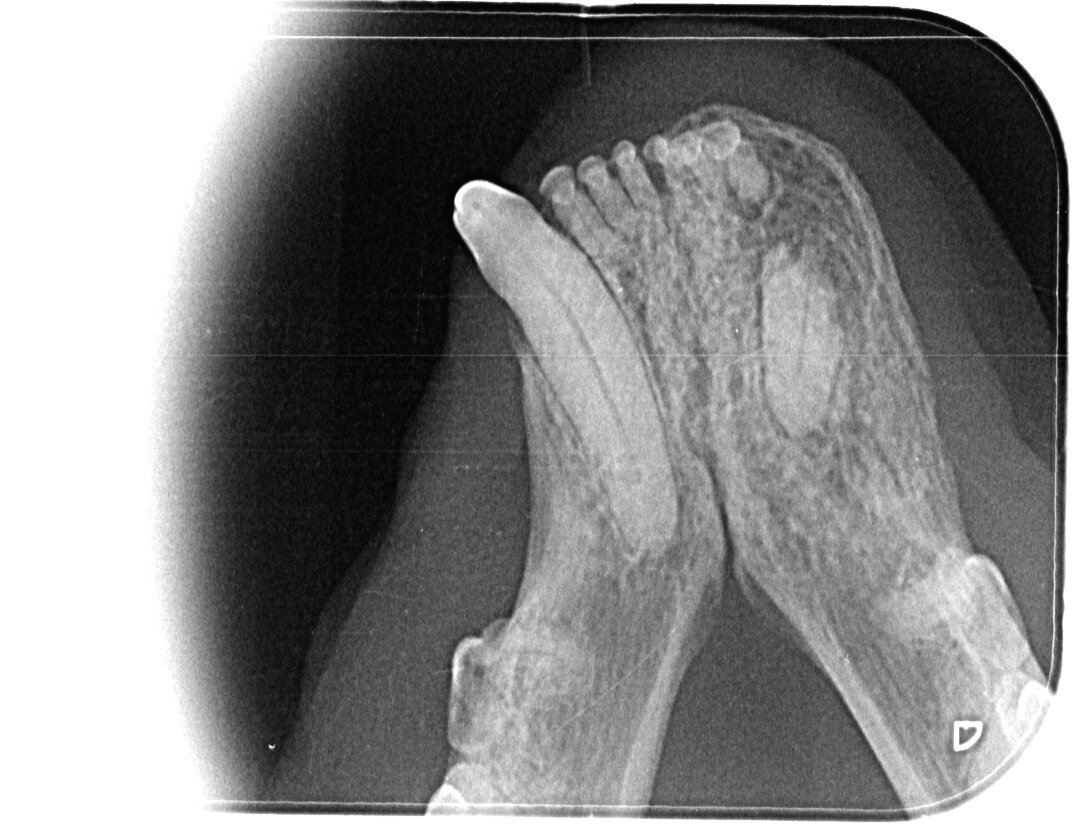

Рентген нижней челюсти. Справа видно, что зуб сломан, а корень остался внутри

Объем операции до последнего был не ясен. Только введя животное под наркоз врачи сделали рентген его зубов и определили сколько нужно будет удалить кроме сломанного клыка. Мы заплатили 30тыс руб за операцию и нахождение в стационаре. В итоге Мите удалили 5 зубов.